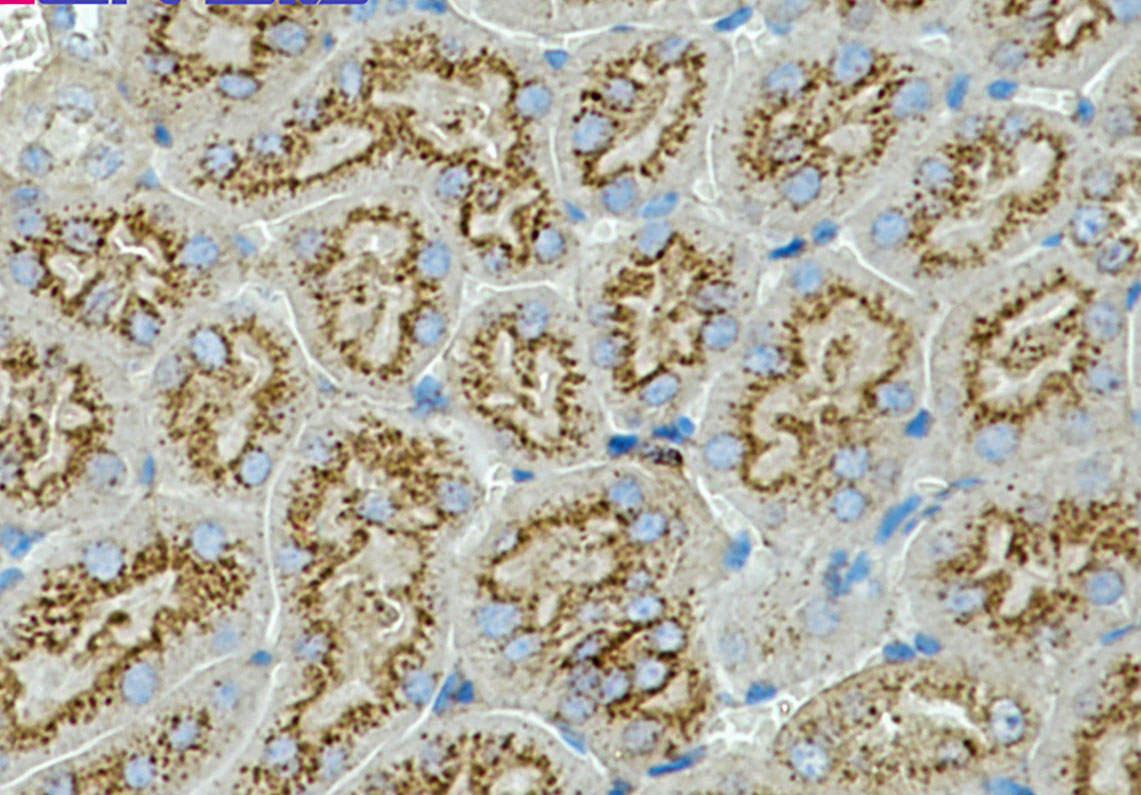

Product Image

IHC | 1/50-1/100 |

Application Key:WB - Western Blot | IHC - Immunohistochemistry | ICC - Immunocytochemistry | FCM - Flow Cytometry | ELISA - Enzyme-linked Immunosorbent Assay | IP - Immunoprecipitation